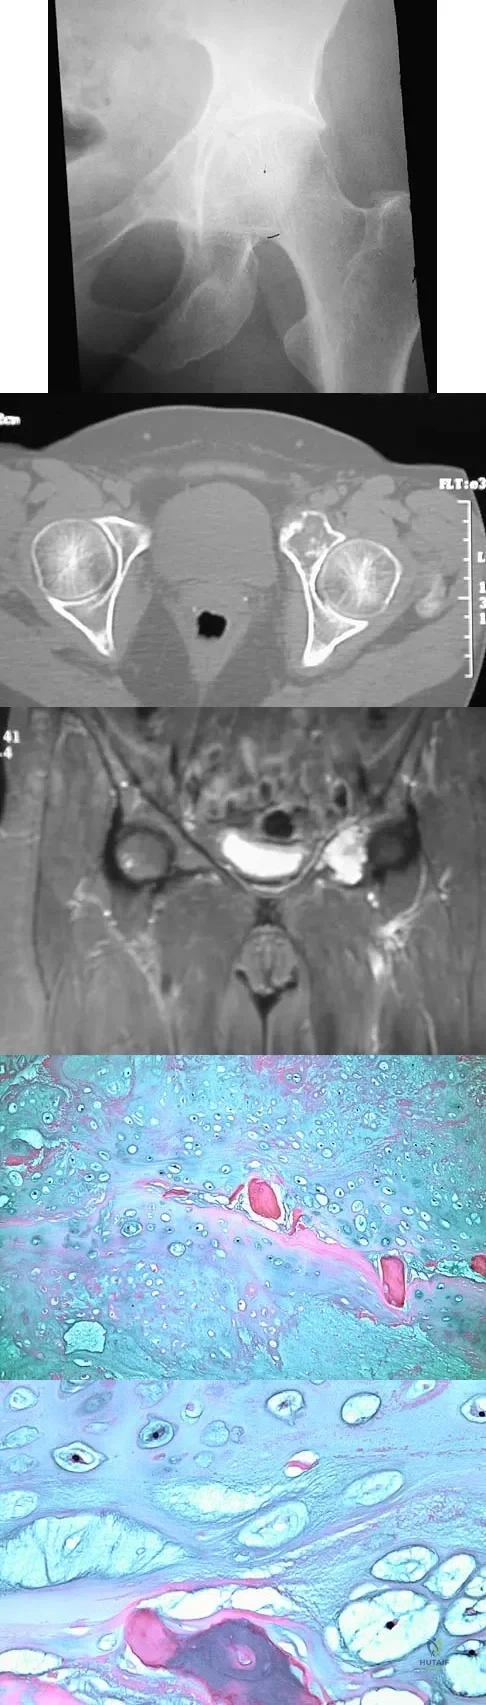

Question 75

A 43-year-old woman has had pain in the left hip for the past 2 months. A radiograph, CT scan, MRI scan, and biopsy specimens are shown in Figures 16a through 16e. What is the most likely diagnosis?